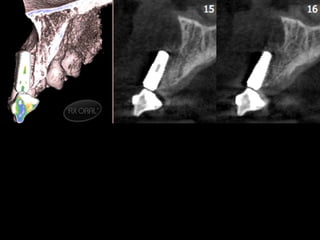

Tomografía computarizada

De seno maxilar corte sagital.

Area de implantación

Dentaria.

Material osteoconductor

para elevar el piso antral

Nuevo piso del seno y su

margen de seguridad para

contener el implante

dentario

Antro maxilar visto desde la cara interna del un hueso

Aparentemente normal

Seno maxilar aumentado de tamaño por

neumatización y edentulosis.

No compatible para aplicación de

implantes por exposición del mismo a la

luz del antro.

Colocación de material biológico o

no para aumentar el espesor del

piso y poder contener implante

dentario en un lecho de “hueso

sano”.

Uno de los fenómenos fisiológicos más comunes es la falta de hueso en el

Piso del antro de Highmore, secundario a la neumatización de los senos y

Que en muchas ocasiones aproxima el piso antral al proceso alveolar, por

Lo que sobre todo en pacientes jóvenes es factible dar volumen a este

Área con la aplicación de injerto de hueso humano, equino o derivados de

arcillas de sílice. Las indicaciones de usar uno u otros depende de la experiencia

Clínica del operador.